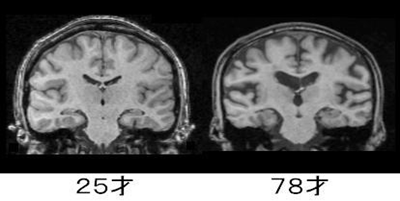

■ MRIから見える“脳の変化”

脳の老化を理解するときに参考になるのが、若年と高齢の脳を比較したMRI画像です。

例えば、25歳と78歳の脳を比べると、次のような違いが確認できます。

- 脳溝(しわ)が深くなり、隙間が広く見える

→ 神経細胞や結合の減少による体積変化の表れ。

- 脳室(脳の中心にある空洞)が大きくなる

→ 周囲の脳組織が萎縮すると、相対的に脳室が拡大して見える。

白質(神経細胞同士の連絡路)の変化は視覚的には分かりにくいものの、こちらも加齢の影響を受けます。

白質のつながりが弱くなると、情報処理のスピードが落ちたり、注意の転換がしにくくなったりすることがあります。

上の画像は、25歳と78歳の脳のMRI(冠状断)です。

健康長寿ネット(https://www.tyojyu.or.jp/net/kenkou-tyoju/rouka/nou-keitai.html)のものを使わせていただいています。